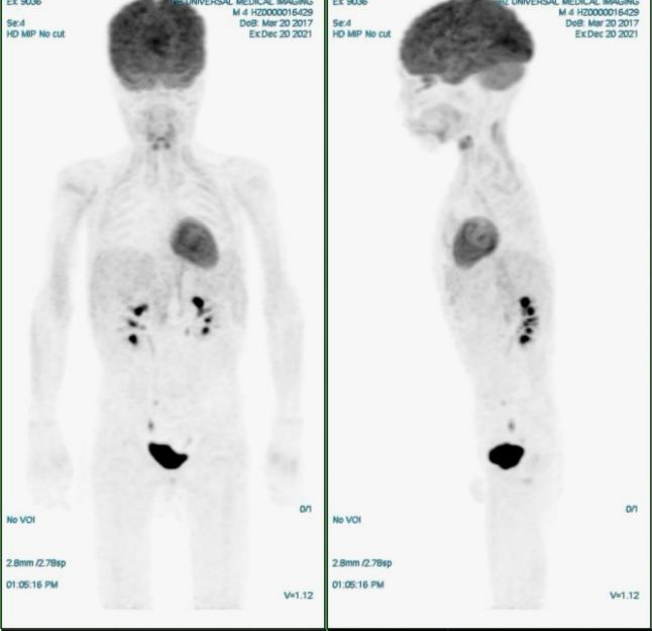

PET/MR(2021.1.11)

腹膜后右侧肾上腺区不规则团块,FDG代谢增高,考虑恶性病变,神经母细胞瘤可能性大,建议结合病理;腹膜后腹主动脉右旁数枚肿大淋巴结,FDG代谢增高,考虑转移;全身骨骼FDG代谢弥漫性增高,考虑骨髓浸润。

放疗后复查:2021.12.21PET/MR:术区未见明确肿块,FDG代谢未见明显异常;全身多处骨骼局部骨质信号异常,FDG代谢未见异常增高,考虑骨转移治疗后改变。

疗效评估:CR。